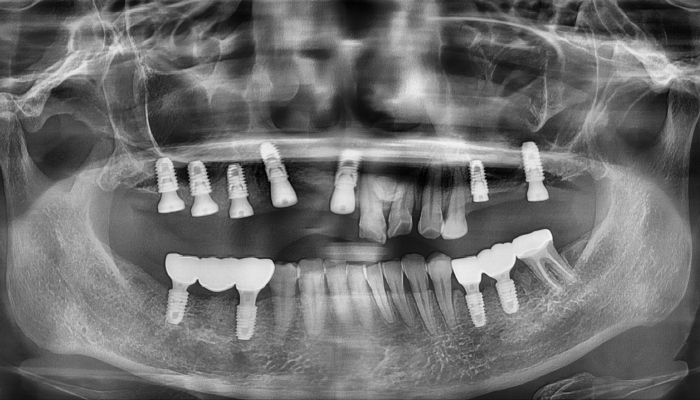

뼈이식 임플란트 전후 사례

• 식립 전

식립 후